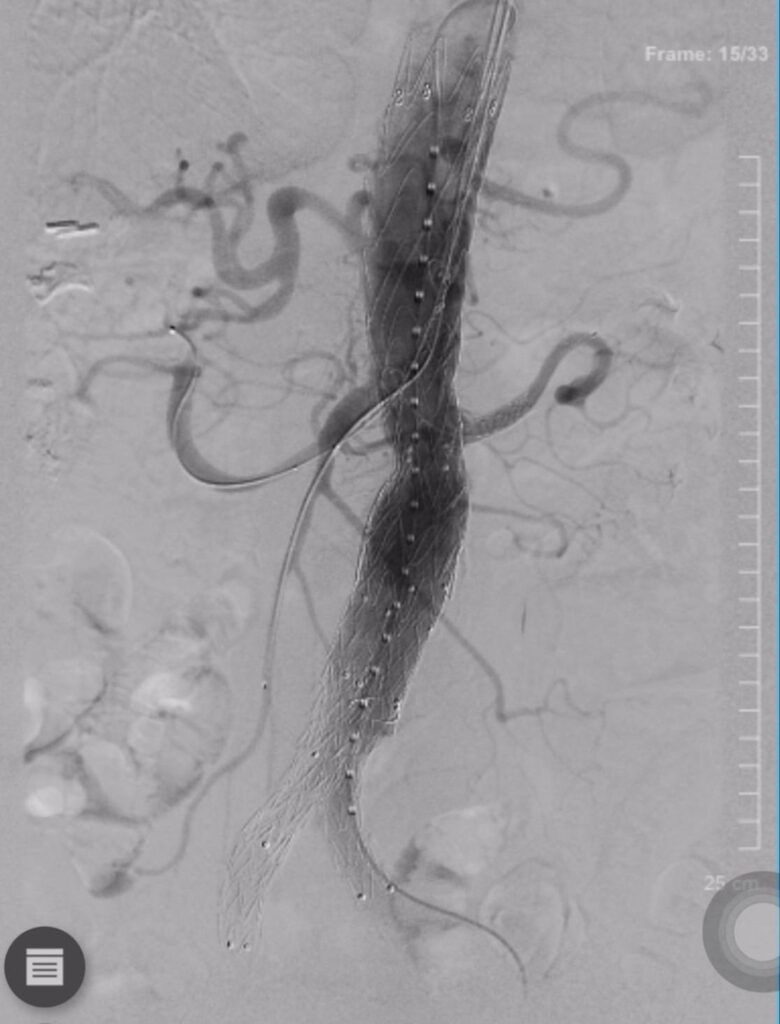

การผ่าตัดดังกล่าวใช้เทคนิค PMEG EVAR (Physician-Modified Endograft Endovascular Aneurysm Repair) ซึ่งเป็นนวัตกรรมขั้นสูงในการรักษาโรคหลอดเลือด โดยเป็นครั้งแรกที่โรงพยาบาลหาดใหญ่สามารถดำเนินการได้สำเร็จ ถือเป็นก้าวสำคัญในการยกระดับศักยภาพการรักษาโรคหลอดเลือดของโรงพยาบาลหาดใหญ่และพื้นที่ภาคใต้